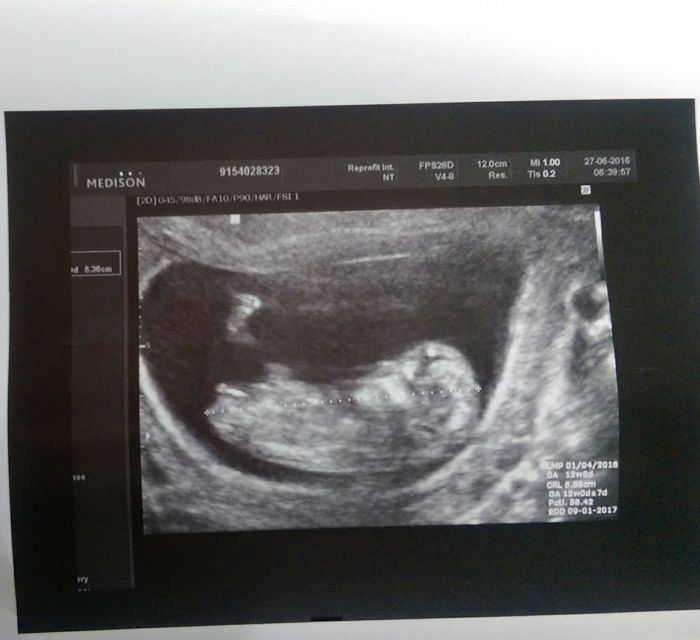

Ja som dneska absolvovala screening,jsem v 12+3tt,miminko sa zatim vyvija v poradku :) a na 95% cakame holcicku. Jsem za to rada,pretoze kdyby to byl kluk stale by som v nom videla nasho anjelika.